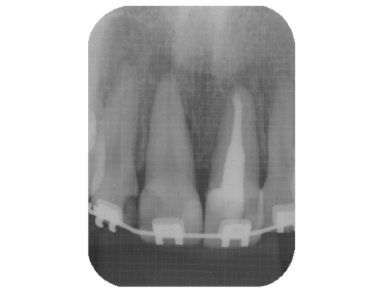

緊密な根管充塡

清潔な無菌的な根管の清掃が終了したら、緊密に根管充塡を行います。レントゲンで白く写る部分です。

根管治療の最後の処置です。根管の解剖学的な形態、彎曲度合い等によって数種類の根管充塡システムを当院では使い分けています。

また、最近はMTAセメントによる根管充塡も非常に予後がよく、取り入れています。

- 根の治療は終わったと言われたそうですが、、、、